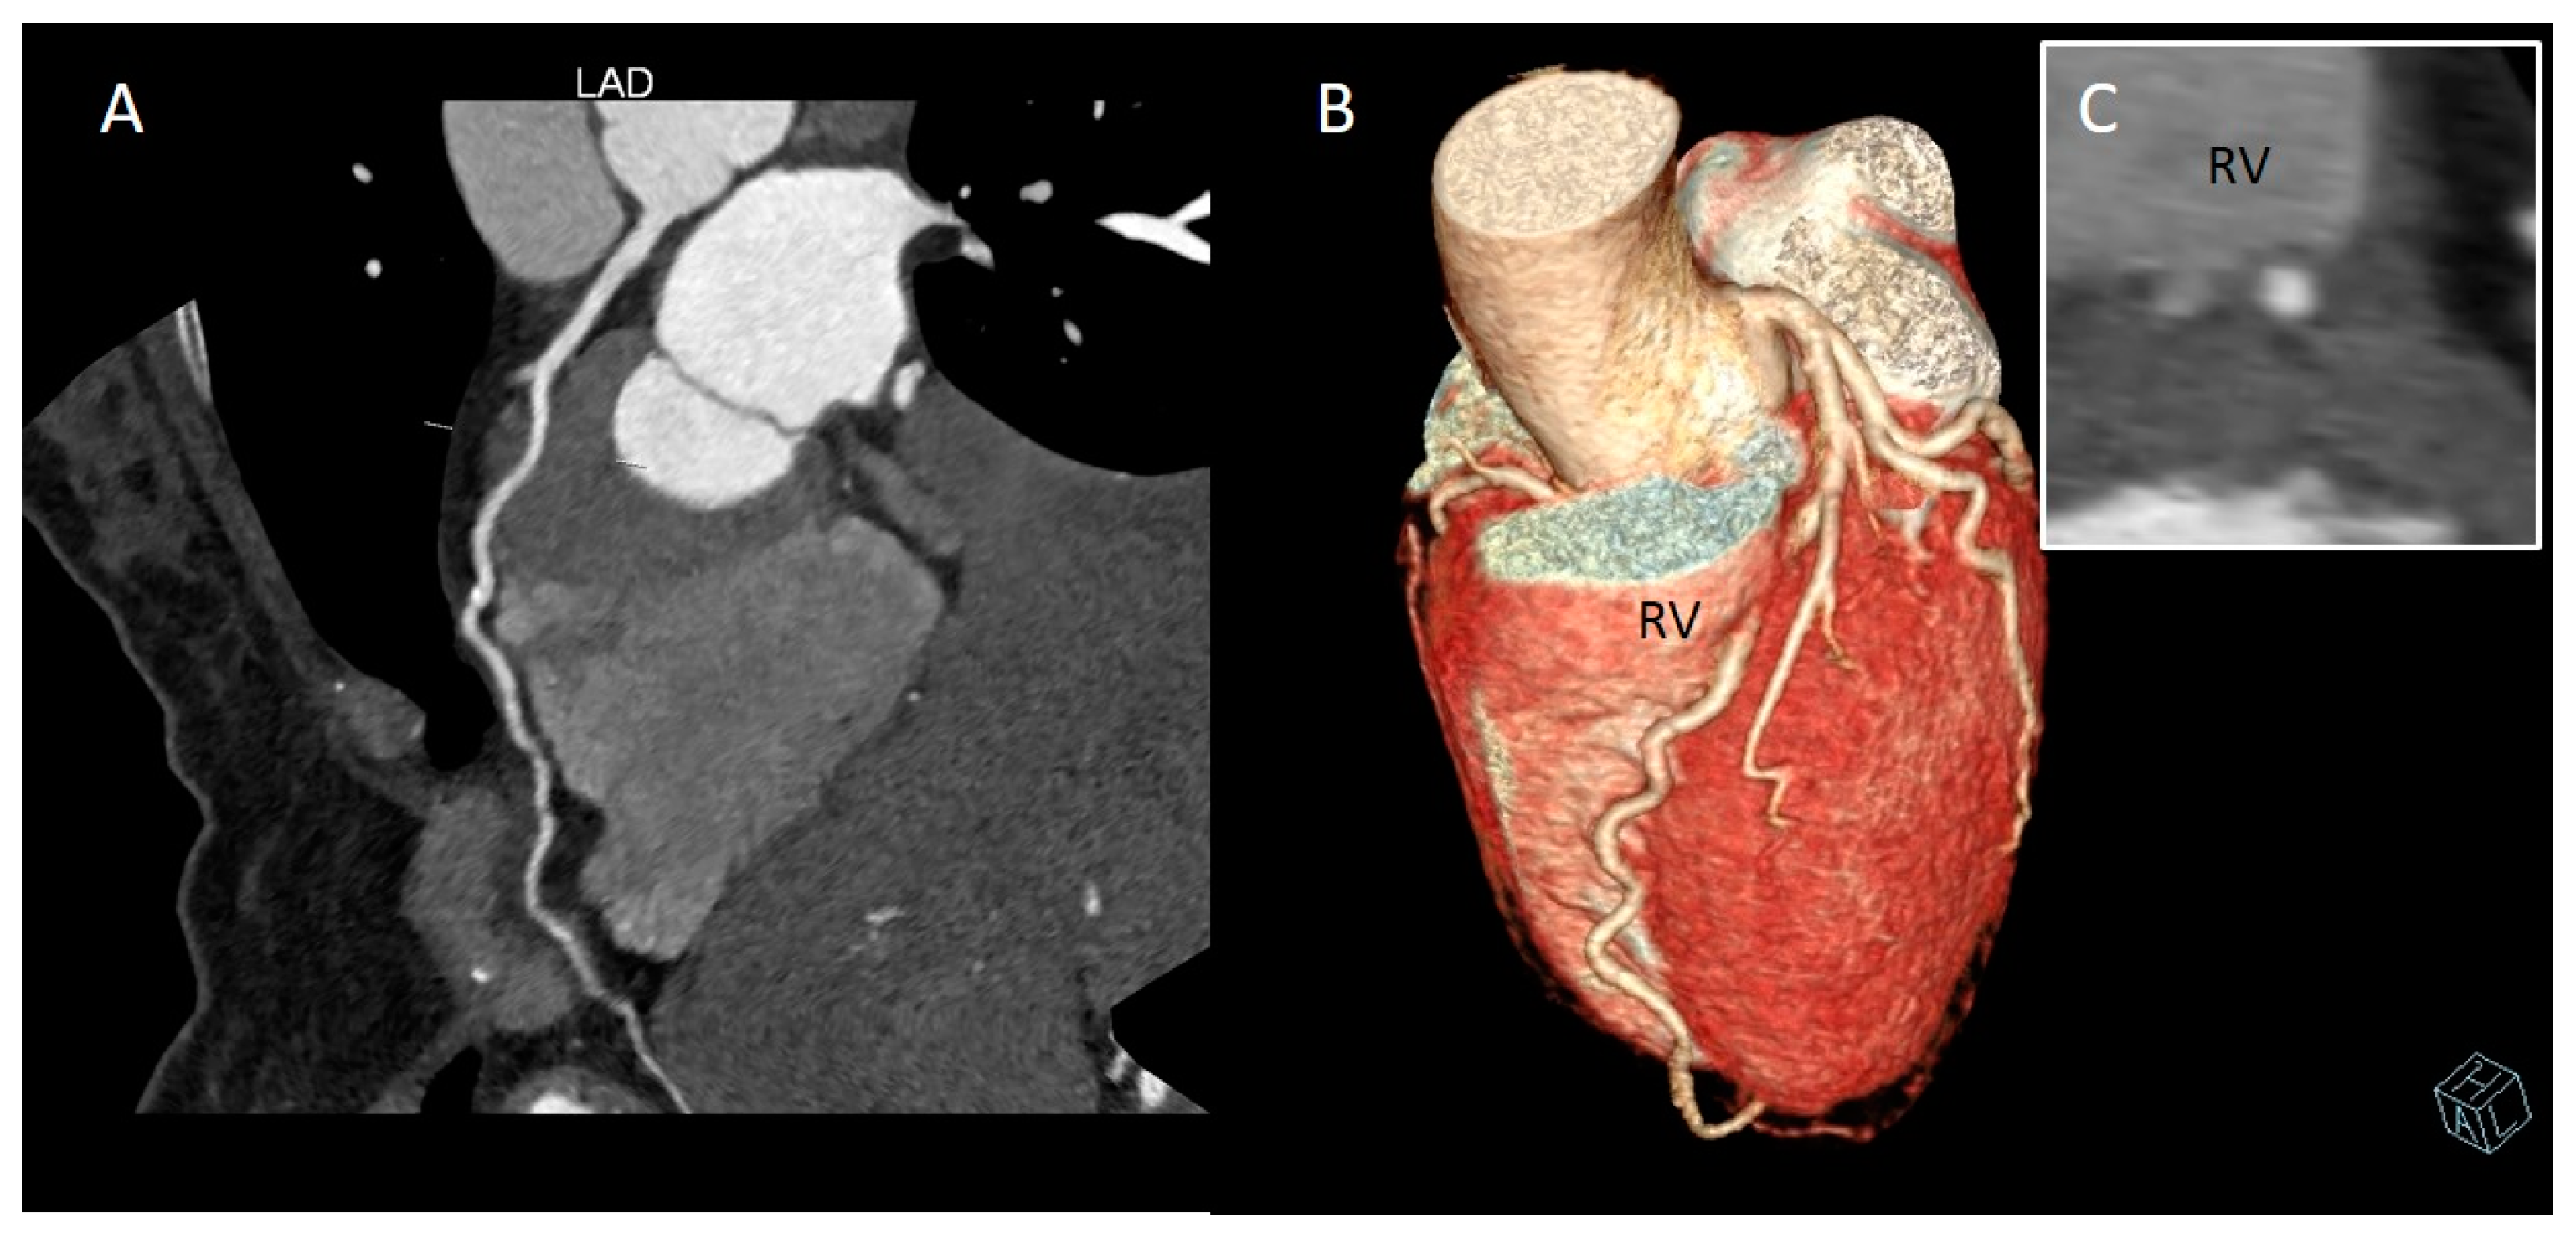

2. CCTA Imaging Protocol

3. Role of CCTA: Anatomical Evaluation